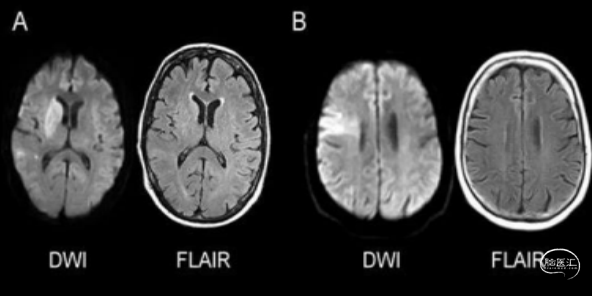

根据发病3小时内或4.5小时内时间窗CT评估后进行评估溶栓外,对醒后卒中或超4.5小时时间窗的患者,在具备CT和核磁共振设备的医院可进行组织窗评估,对醒后卒中从睡眠中点至入院在9小时内的患者经组织窗评估存在错配:即CT无病灶,DWI有病灶而FLAIR无明显改变,说明在4.5小时时间窗内,明确责任病灶,仍然可积极进行静脉溶栓。

组织窗评估——DWI-FLAIR 错配:

存在 DWI-FLAIR 错配定义:DWI 显示高信号,FLAIR 信号改变不明显区域.

DWI-FLAIR 错配表明组织缺血时间在 4.5 小时内,可以作为静脉溶栓筛选指标,适用于醒后脑卒中患者进行溶栓决策。

不存在 DWI-FLAIR 错配:

DWI和FLAIR上相应区域均可见明显高信号 。适用于醒后或超时间窗脑卒中患者评估,不存在 DWI-FLAIR 错配说明不能进行静脉溶栓,溶栓获益较小而且出血风险增加。